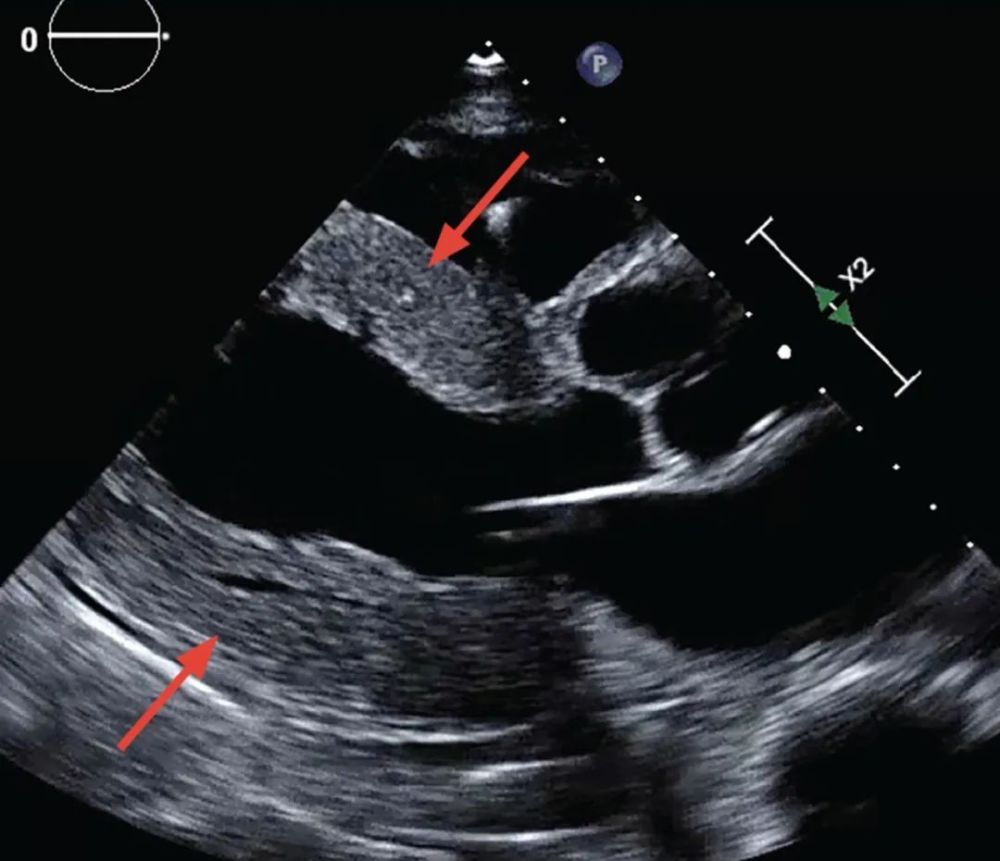

超声心动图显示左心室射血分数为55%,同心性左室壁肥厚,壁厚15mm(图1)